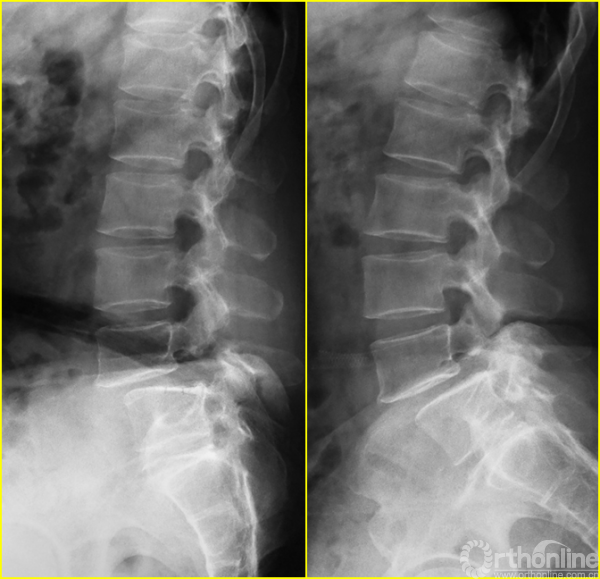

腰5椎体前滑脱I-II°,峡部裂,动力位显示腰5-骶1节段明显失稳